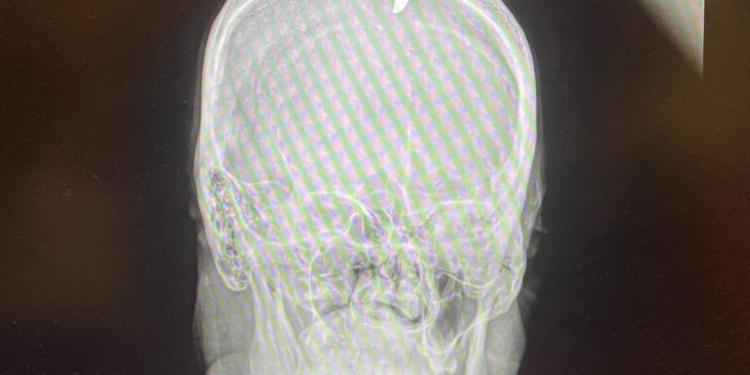

Jean-Robert Fleury, journaliste au Nouvelliste, spécialiste des questions judiciaires, a été touché à la tête par une balle perdue, mercredi 16 juillet, alors qu’il se trouvait sur la galerie de son domicile à Méyotte, quartier situé dans la commune de Pétion-Ville. Le projectile a atteint le sommet de son crâne. Pris en charge rapidement, il a été transporté à l’hôpital où il a reçu les soins que nécessitait son cas. Une radiographie a révélé que la balle a perforé sa tête, provoquant une grave blessure. Pour le moment, Jean Robert Fleury va mieux et se repose.